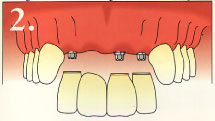

This is an example of multiple dental implants.

This is how the finished result would look.